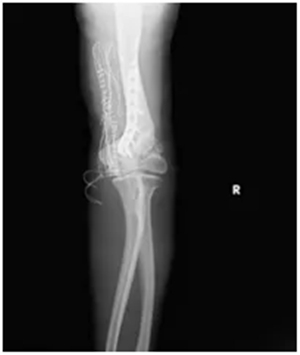

肘关节外翻角度从术前的30°左右,成功矫正到10°左右;

肘关节的伸直、屈曲活动范围,比术前明显改善;

X线复查显示:钢板固定位置十分合适,骨头对位良好;

第二步“肱骨截骨矫形+钢板固定”:通过精准截骨,纠正肘关节的外翻畸形,再用钢板牢牢固定,让关节恢复正常的力学结构。